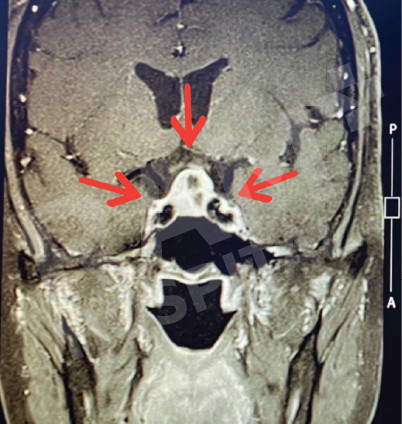

磁共振成像(MRI)可清晰、细致地显示垂体的异常病变,精准定位垂体腺瘤的位置;结合静脉造影增强检查,还能明确腺瘤的具体位置与病变性质,同时清晰呈现脑部周边组织及鼻窦的情况。这一项检查结果可为制定诊疗方案、随访评估垂体腺瘤的治疗效果,乃至规划手术方案提供明确、可靠的依据。

| 术前 | 术后 |